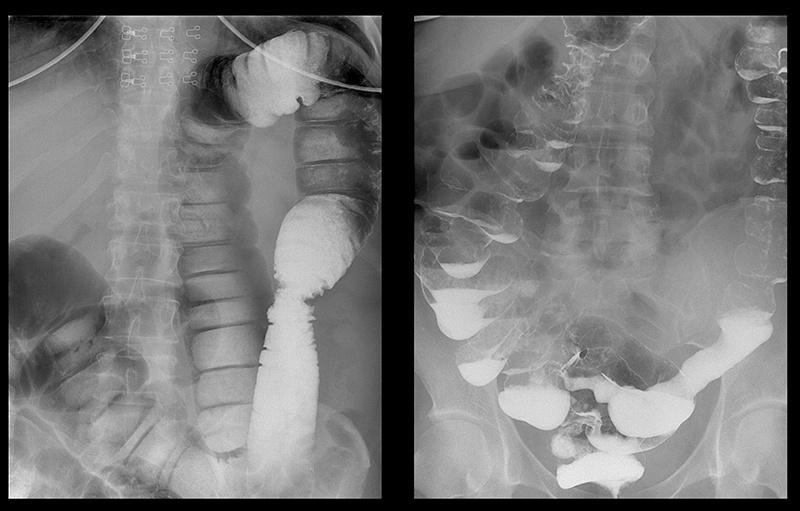

Mire las fotografías de los órganos de personas que inicialmente tenían mal aliento, estreñimiento y acidez de estómago, y terminaron recibiendo el informe de un patólogo.

“Cáncer de colon en una mujer con estreñimiento frecuente

"Ecografía de cálculos fecales en el colon"

"Etapas del cáncer de recto que se desarrollan en 1 o 2 años"